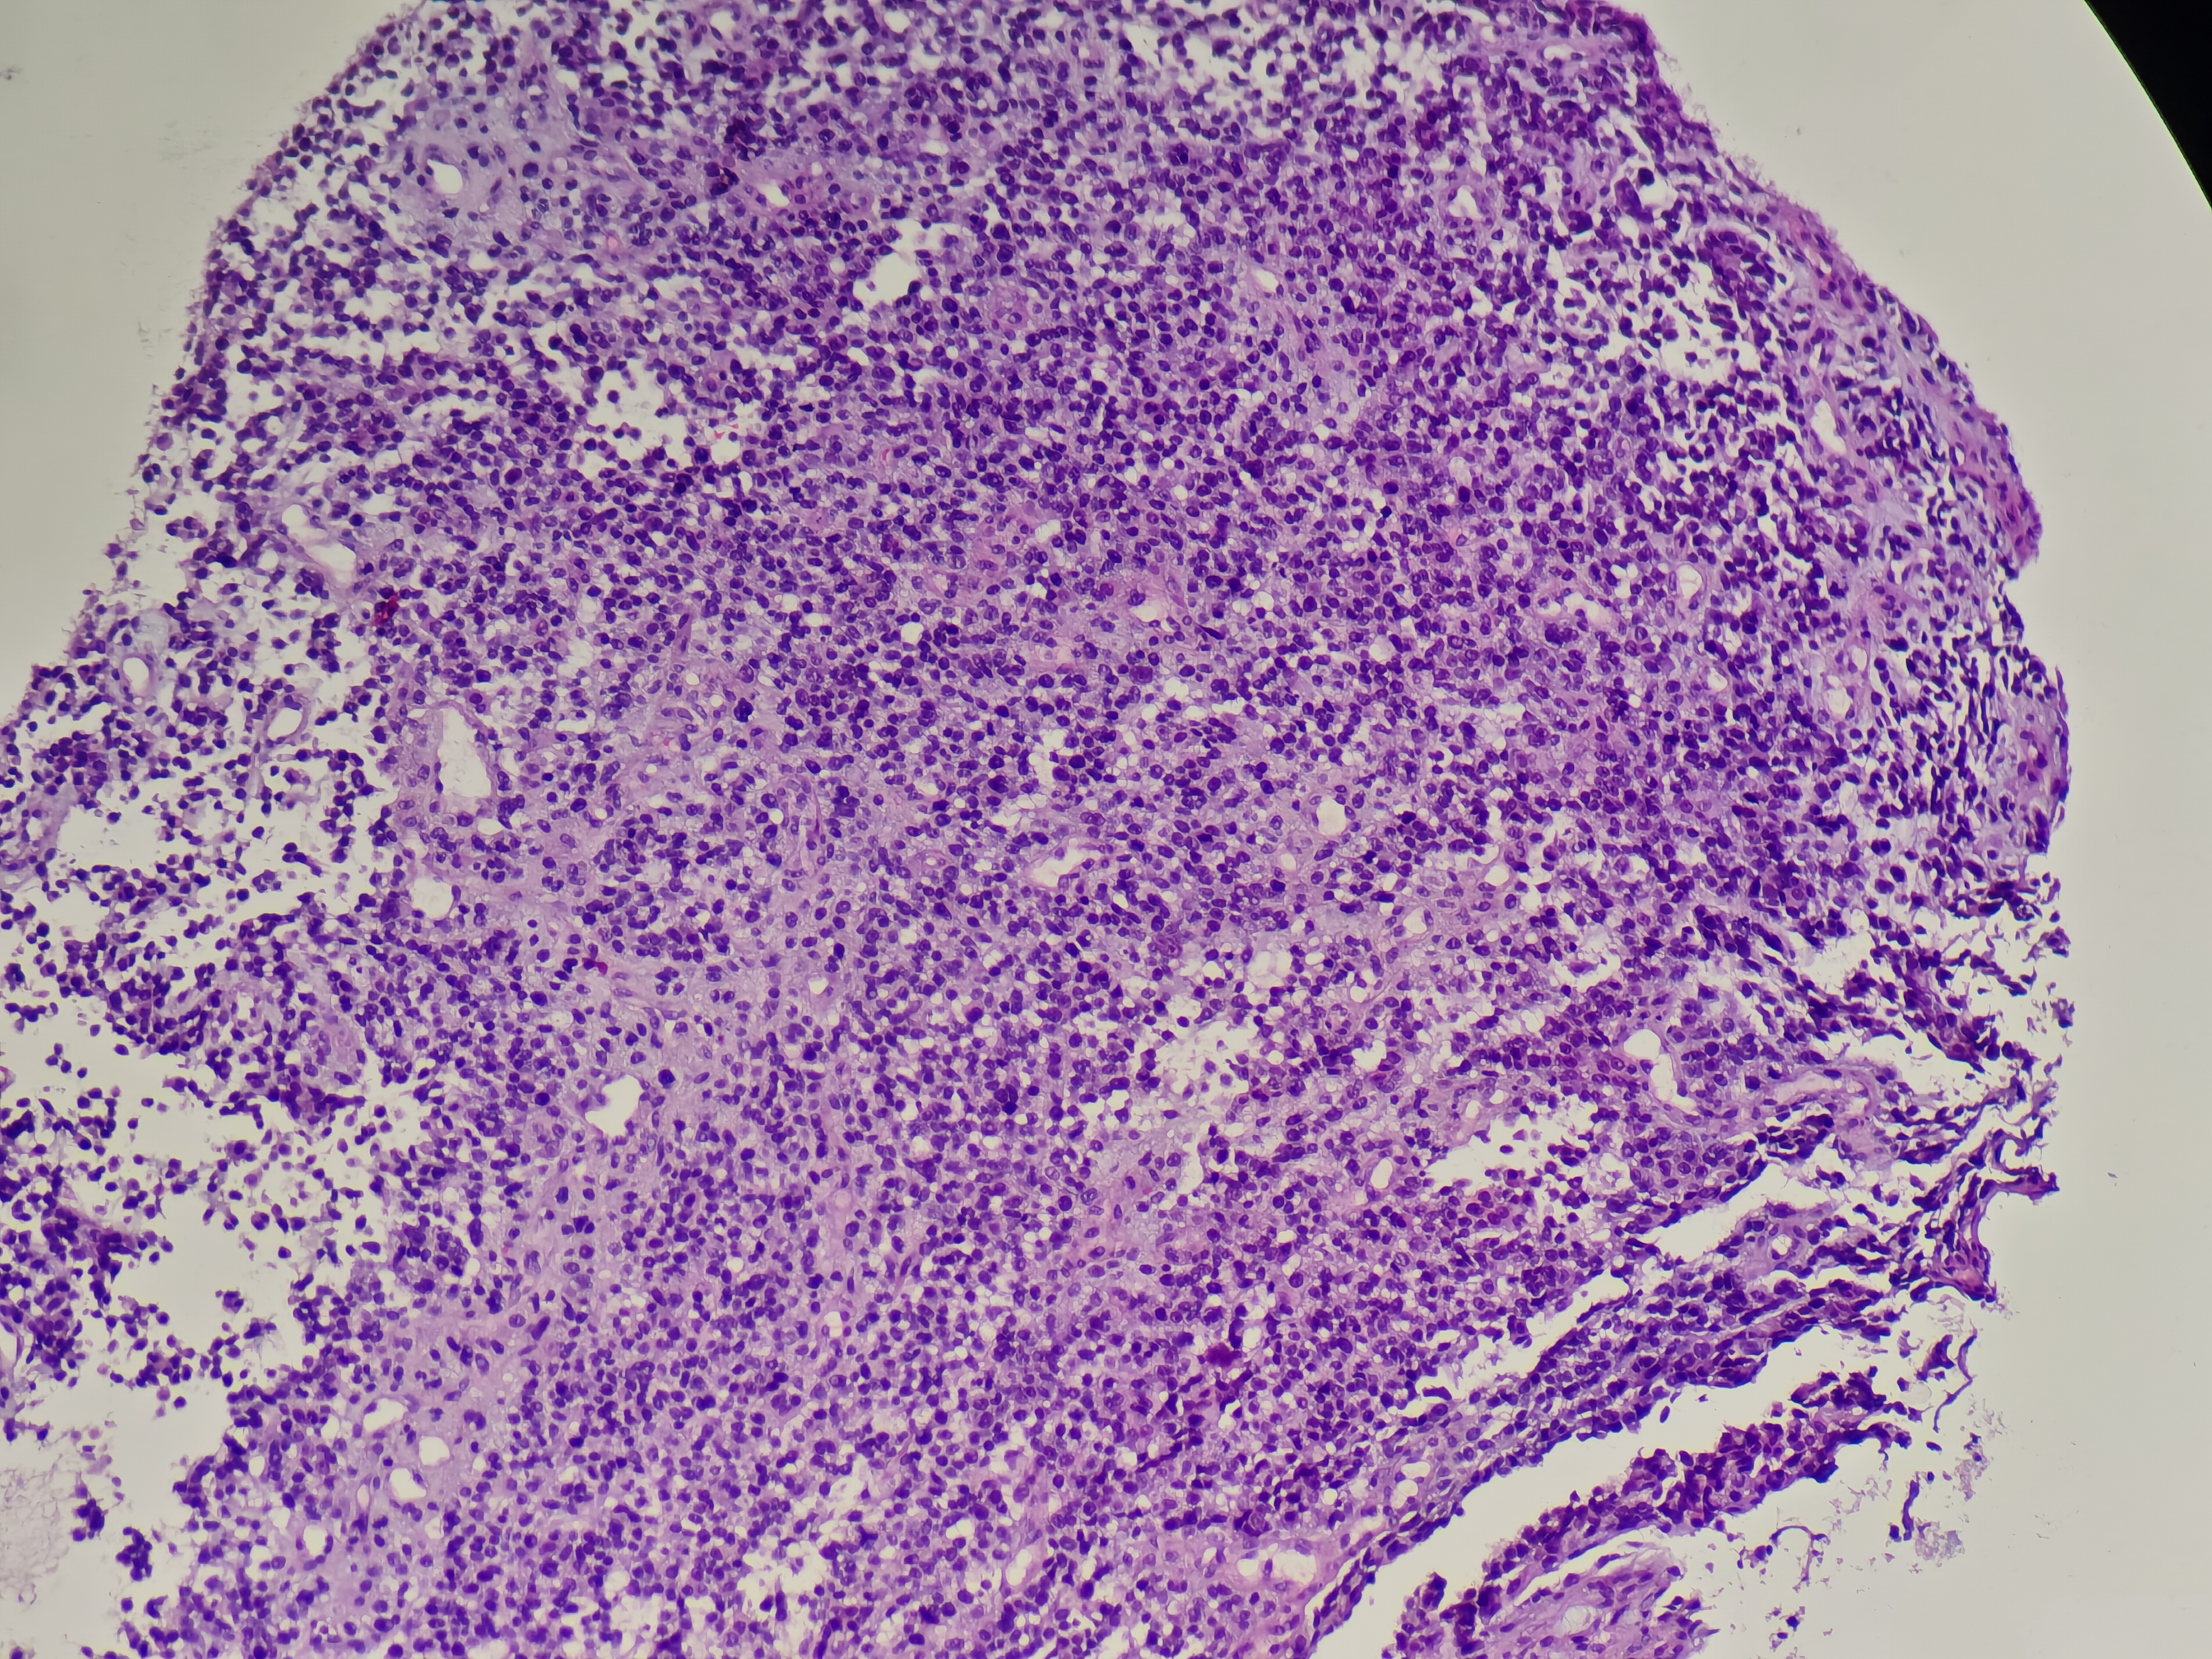

食管癌

食管距门齿33~38cm处可见环管腔半周隆起性病变,表面破溃,易出血,活检6块,质脆

食管活检

灰白软组织6块,直径0.1~0.2cm

请教老师,这个报什么癌?

图2